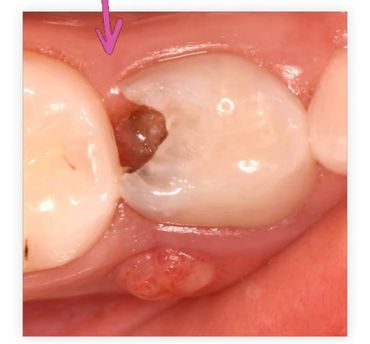

Comenzamos con el expediente y una evaluación detallada de sus dientes y encías, utilizamos una cámara intraoral, que nos permite ver de cerca cada diente y detectar cualquier problema a tiempo.